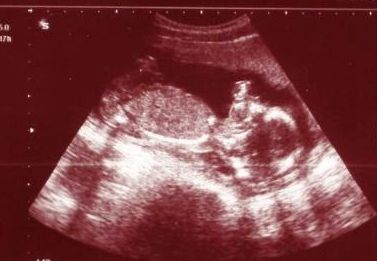

Шевеления во многом зависят от размеров и темперамента будущего малыша. Отчетливо движения малыша можно увидеть на УЗИ, при этом малыш активно двигается, у него отлично различимы все части тела и даже выражения личика.

В этом сроке можно также узнать, кто живет в вашем животике – девочка или мальчик. В 16 недель вполне точно можно определить пол.

УЗИ на 16-й неделе беременности